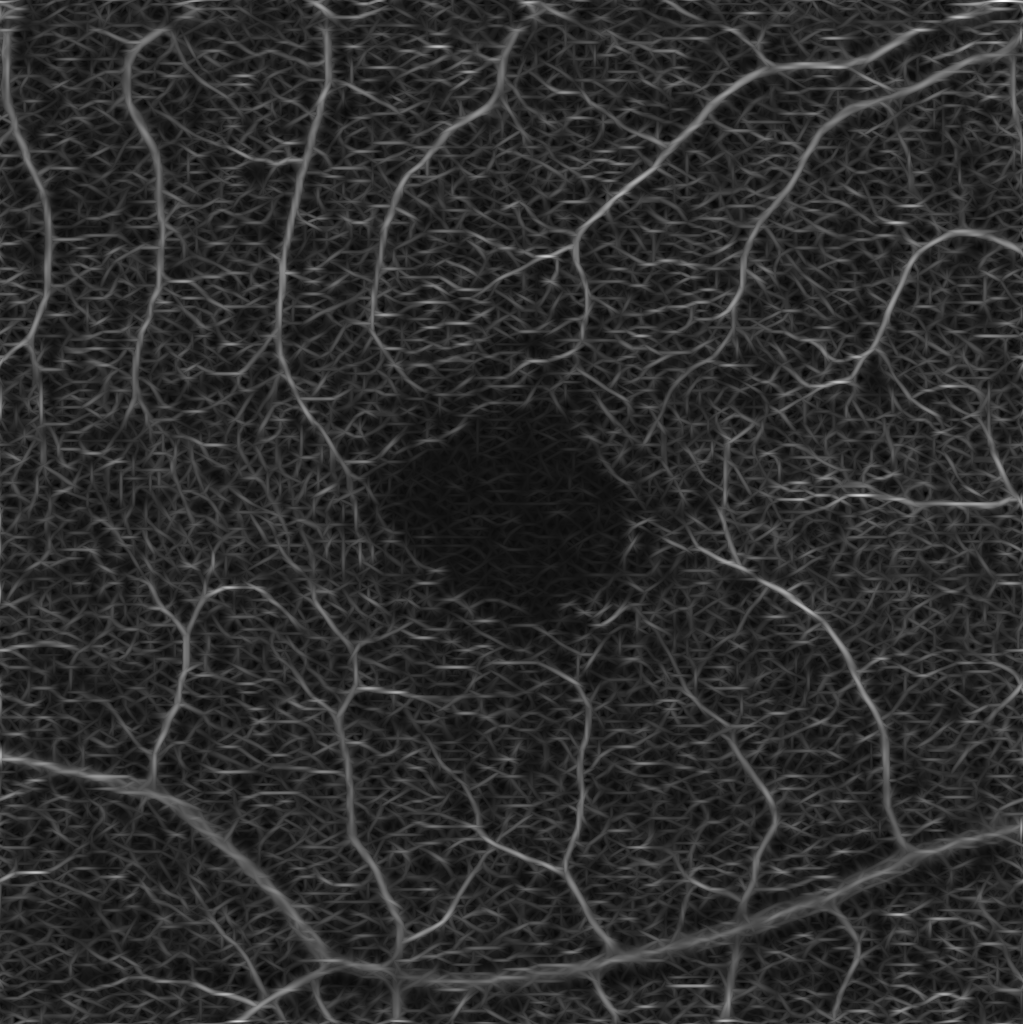

Our image segmentation is divided into three subtasks: the identification of small and big vessel and the FAZ. The final result, see Figure 2(b), is obtained by uniting the binary images with the small and big vessels and subsequently using the FAZ segmentation as a mask that excludes that area.

Refer to caption

(a) Original image

(b) Final segmentation

Figure 2: The combined substeps described in Sections 2.1 and 2.2 yield the final image.

The visual results of the segmentation are very good: small vessels are identified accurately, branches are preserved and the ratio of the vessel diameter is pictured realistically. Furthermore, small non-perfusion areas around larger vessel and vascular angles are also depicted truthfully. See Figure 4 for a visualisation of some details.